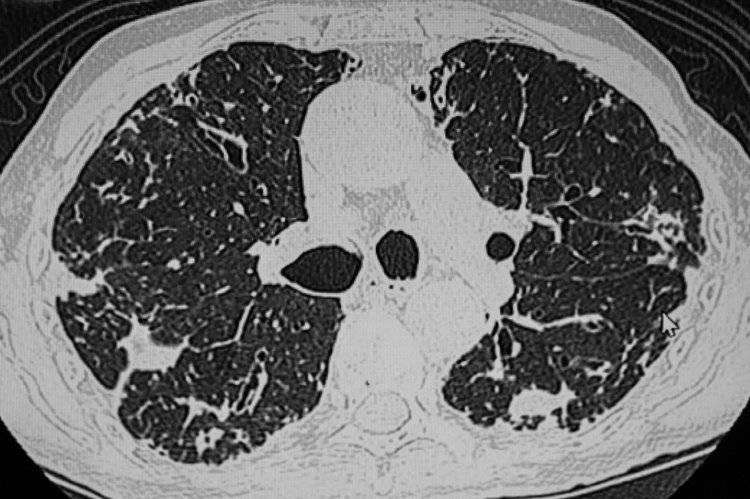

首先是肺结节。它指的是肺部出现的直径≥3cm的病灶,在影像学检查中表现为密度增高的阴影。中国医学科学院肿瘤医院山西医院胸外科主任廉建红指出,如今检查仪器精密度大幅提升,一些微小结节也能被及时发现,这些结节大多处于早期阶段,无需过分紧张。尤其是直径8mm以下的结节,恶性概率极低,临床一般建议以定期随访为主。需要注意的是,年龄>45岁的成年人属于肺结节高发人群,建议每年进行一次肺部CT检查,这能及时发现早期潜在问题,对结节的防治意义重大。